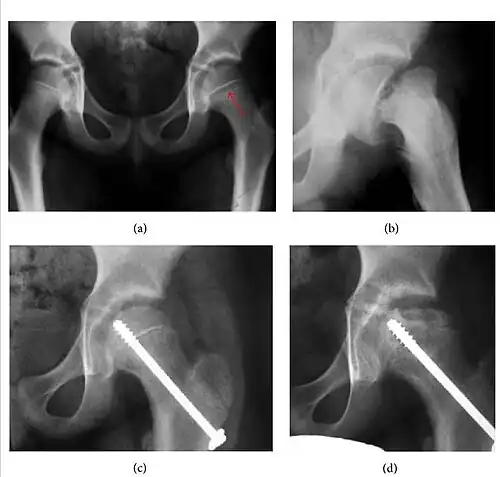

Plain radiography allows us to categorize the hip as normal or dysplastic or with impingement signs (pincer, cam, or a combination of both). Besides these, pathologic processes like osteoarthritis, inflammatory diseases, infection, or tumors can also be identified (Figure 1).[1]

Figure 1.

Radiography in normal hip

X-ray in pincer impingement type of hip dysplasia

X-ray of cam

Hip in osteoarthritis

Septic arthritis

Slipped capital femoral epiphyses (SCFE) usually affect 11- to 14-year-old adolescents (Figure 4). Radiographs may show widening and irregularity of the physis and posterior inferior displacement of the capital femoral epiphysis. On the AP view Klein’s line, tangent to the lateral aspect of the femoral neck, does not intersect the femoral head indicating that it is displaced. SCFE may compromise the blood supply to the femoral head and cause avascular necrosis, mainly when there is instability between the fragments.[1]

Figure 4: (a) X-ray of a 10-year-old child with left hip pain. It was considered normal at emergency despite the widening of the left physis (arrow). Two weeks later epiphysiolysis was evident (b). Despite appropriate surgical reduction (c) osteonecrosis developed and femoral head collapsed 1 month later (d).[1]